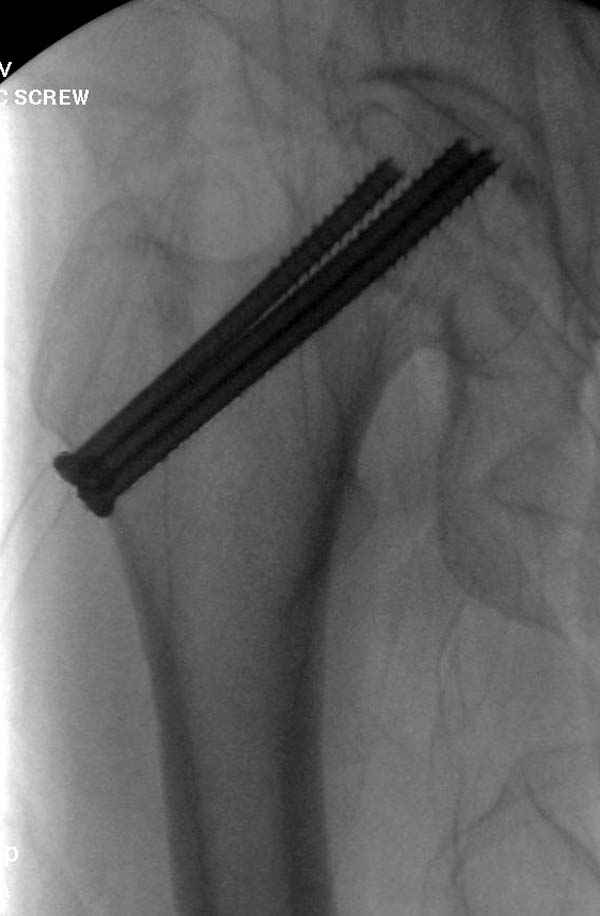

в течение первых 72 часов после перелома, остеосинтез тремя спонгиозными шурупами.

Профилактику дальнейшего раскола неполного перелома шейки провели тремя канюлированными шурупами.

На второй день после выписки упал дома. Снимки приложены. Коллеги рекомендуют удаление шурупа и вытяжение. Что делать?